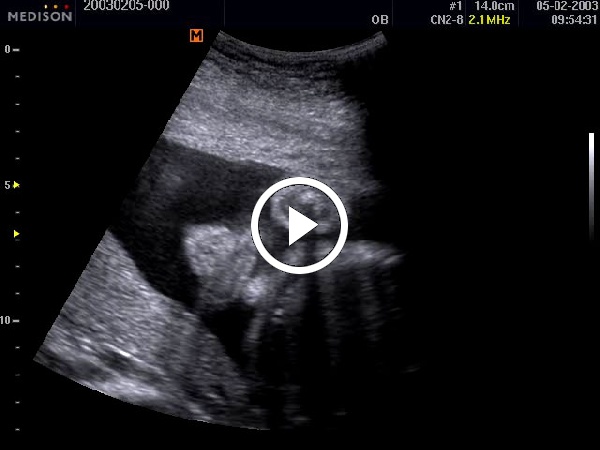

Példák a Cine memória tartalmának visszajátszására:

1. B-mód (2D -mód) Cine képei